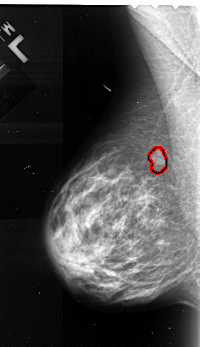

A_1103_1.LEFT_CC

LEFT_CC LINES 4351 PIXELS_PER_LINE 2971 BITS_PER_PIXEL 16 RESOLUTION 42 OVERLAY

FILE: A_1103_1.LEFT_CC.OVERLAY

TOTAL_ABNORMALITIES 1

ABNORMALITY 1

LESION_TYPE MASS SHAPE LOBULATED MARGINS MICROLOBULATED

ASSESSMENT 4

SUBTLETY 4

PATHOLOGY MALIGNANT

TOTAL_OUTLINES 1

BOUNDARY